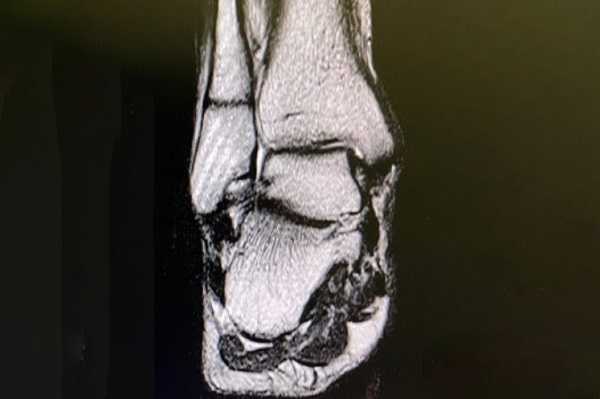

Томограмма голеностопного сустава

3D-модель голеностопа (вид спереди и сзади). Стрелками указаны места переломов